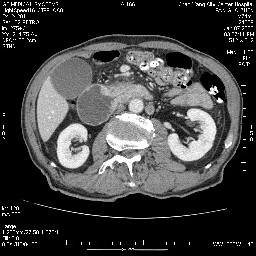

女,74岁,呕吐10余日

壶腹部的占位性病变,考虑为十二指肠癌并梗阻,但脾内多发性低密度区为转移吗?

还有胃、脾之间可见有侧支循环建立。左肾盂积水。

考虑来源于十二指肠水平段的恶性占位,侵及周围组织,特别是胰腺,可见区域淋巴结肿大,左侧下腔静脉畸形。

双肾多发小囊肿;左肾积水。

十二指肠水平段腔内占位伴梗阻,中等度较为均匀的强化,洗脱慢,区域淋巴结显示增多,符合腺癌表现。下腔静脉变异。

十二指肠降段扩张,水平段狭窄成鼠尾状,肠壁明显增厚,胰腺勾突增大成不均匀强化,其内可见低密度区,胆囊增大,1十二指肠水平段腺癌侵犯胰腺勾突可能大,2胰腺癌侵犯十二指肠(只有胆囊增大没有肝内外胆管扩张不好解释)代除外.

十二指肠降段扩张,水平段狭窄成鼠尾状,肠壁明显增厚,胰腺勾突增大成不均匀强化,其内可见低密度区,胆囊增大,1十二指肠水平段腺癌侵犯胰腺勾突可能大,2胰腺癌侵犯十二指肠 。

今日手术结果:胰腺钩突癌侵犯十二直肠,腹腔淋巴结转移.